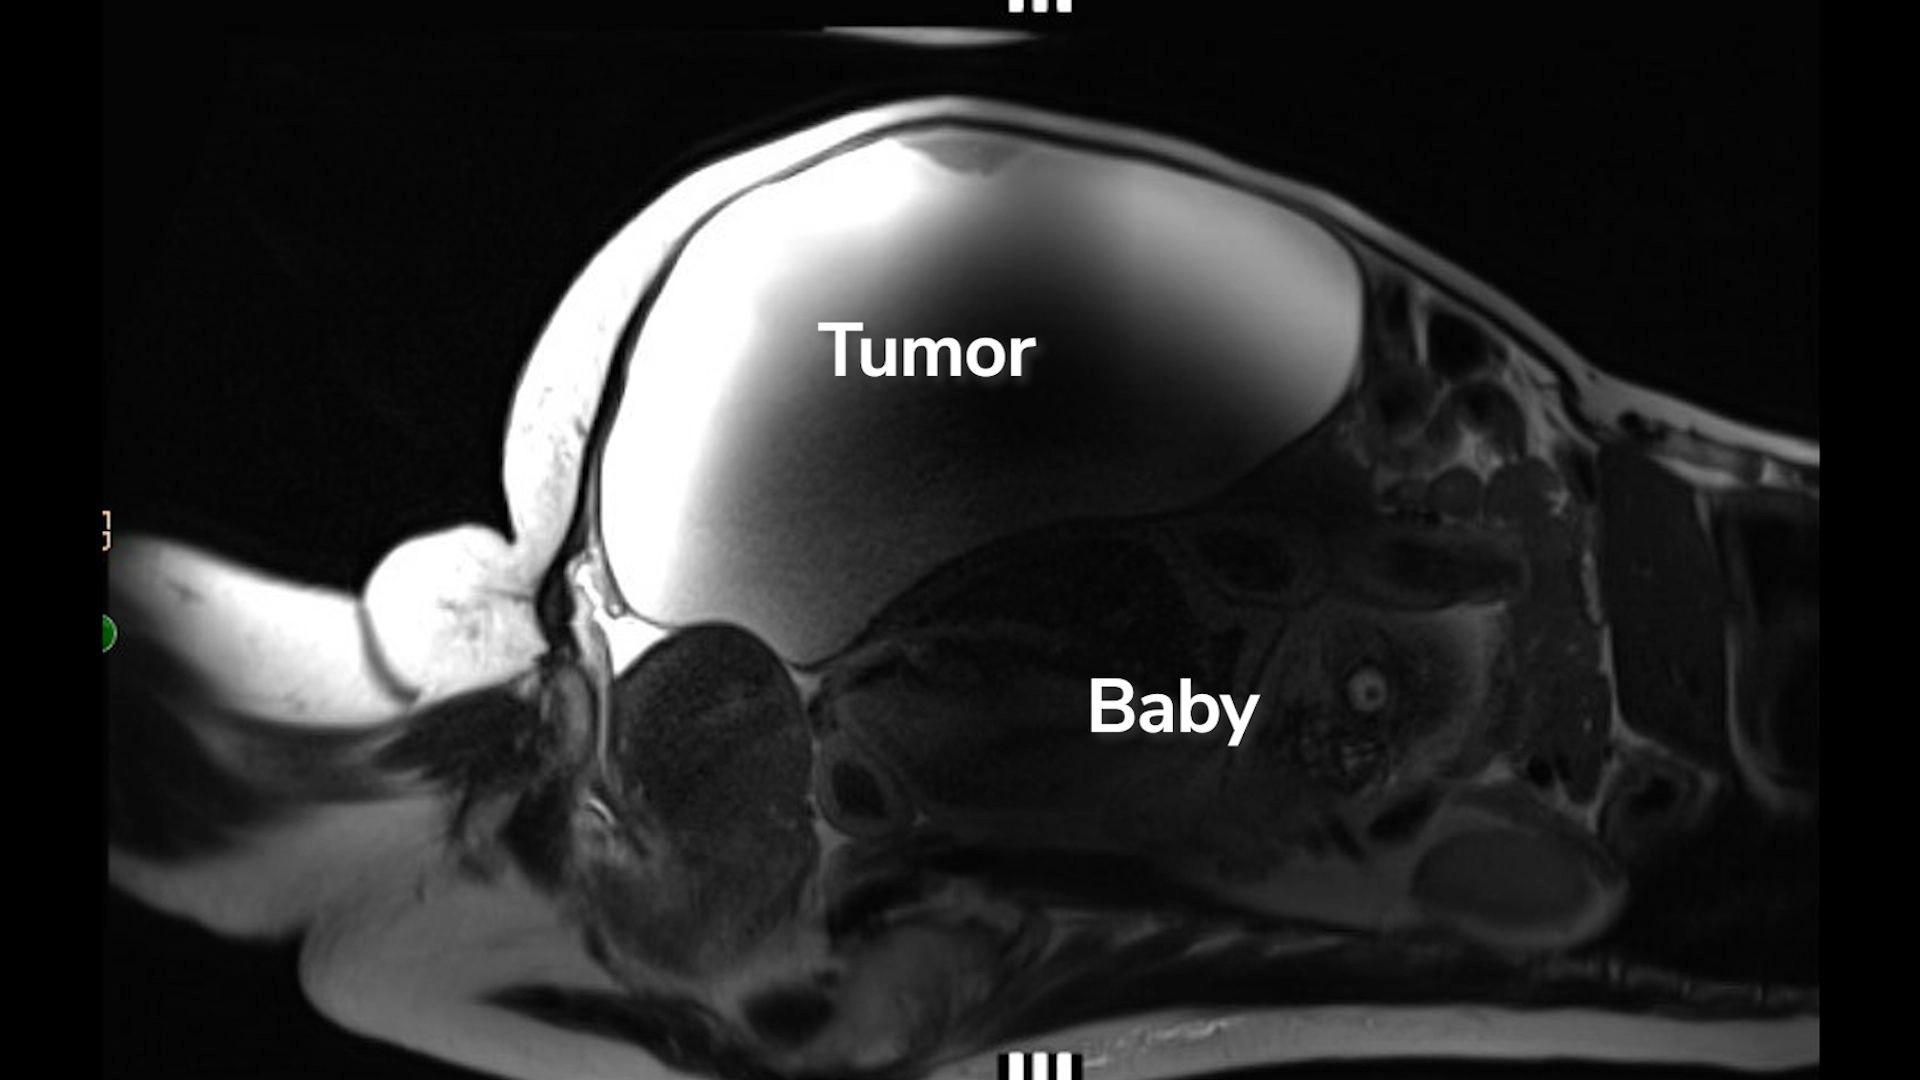

Lopez arrived at the hospital with very high blood pressure, and as medical staff set about treating it, they also ran blood work and body scans, including an MRI and ultrasound. That's when they discovered that Lopez was carrying a rare abdominal ectopic pregnancy. The baby was situated near the liver, with his back half resting on top of the uterus.

"It was the baby growing in her abdomen behind the mass that was pushing everything out," Dr. John Ozimek, medical director of Labor and Delivery and the Maternal-Fetal Care Unit at Cedars-Sinai, said in the video. "So that's the reason she didn't know she was pregnant."